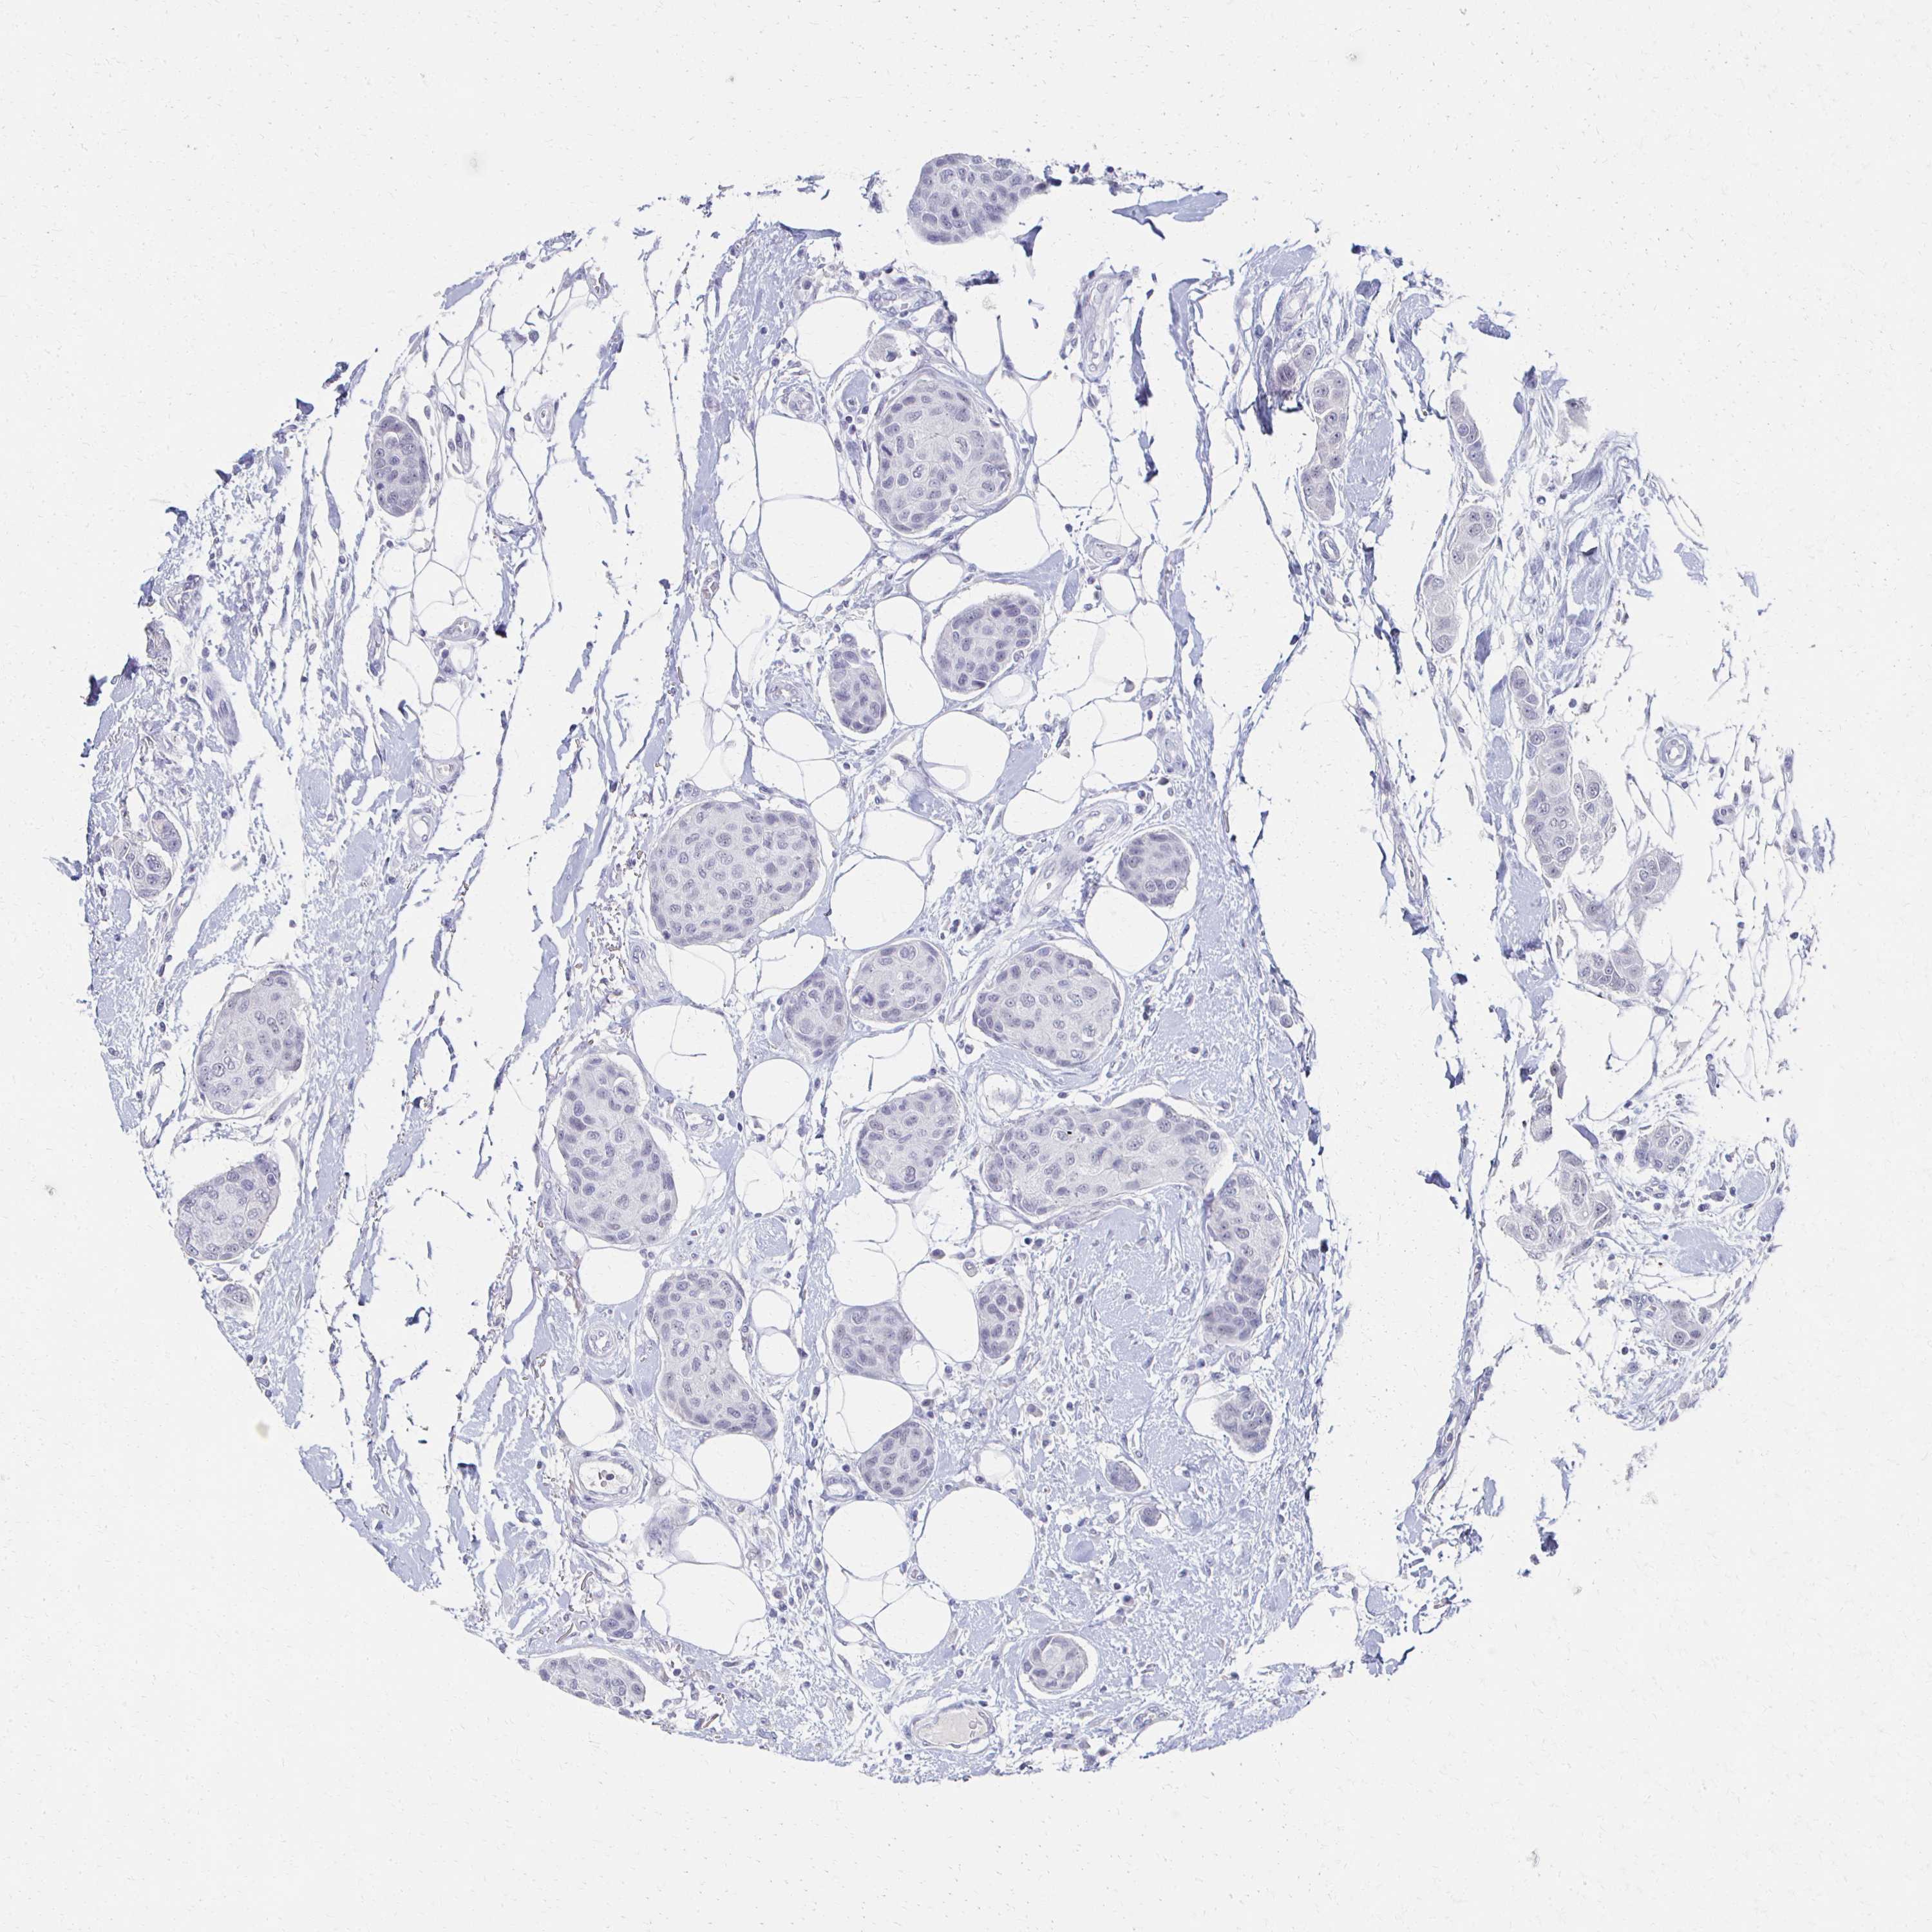

BRCA TCGA BRCA VALIDATION PROTEIN EXPRESSION

Breast cancer

Human cancer